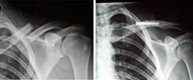

- Fracturas de clavícula

- Luxaciones acromioclaviculares

Las fracturas de clavícula representan del 10 al 16% de todas las fracturas de nuestro esqueleto y son las fracturas más frecuentes de la infancia. Afectan fundamentalmente a su tercio medio (75%) y no suelen producirse por impacto directo sobre ella, sino, por una caída sobre el hombro, el cual transmitela fuerza deformante hacia la clavícula produciendo su fractura.Este tipo de lesión es característico, pues, de aquellos deportes que pueden provocar impactos violentos sobre el hombro como caídas desde bicicleta, motocicleta, patín, skate o deportes de contacto como rugby, hockey hielo, futbol americano, etc.

Las luxaciones acromioclaviculares son producidas por traumatismos en el hombro y producen la separación entre la clavícula y el acromion. La fuerza deformante puede llegar al hombro de forma directa (impacto sobre el hombro) o de forma indirecta tras caída sobre la mano con la extremidad extendida y transmisión del impacto al hombro.Son típicas de la segunda y tercera década de la vida afectando casi siempre al sexo masculino por su mayor predisposición a los deportes de velocidad (motociclismo, automovilismo, ciclismo, esquí) y de contacto (karate, judo, tae-kwon-do).